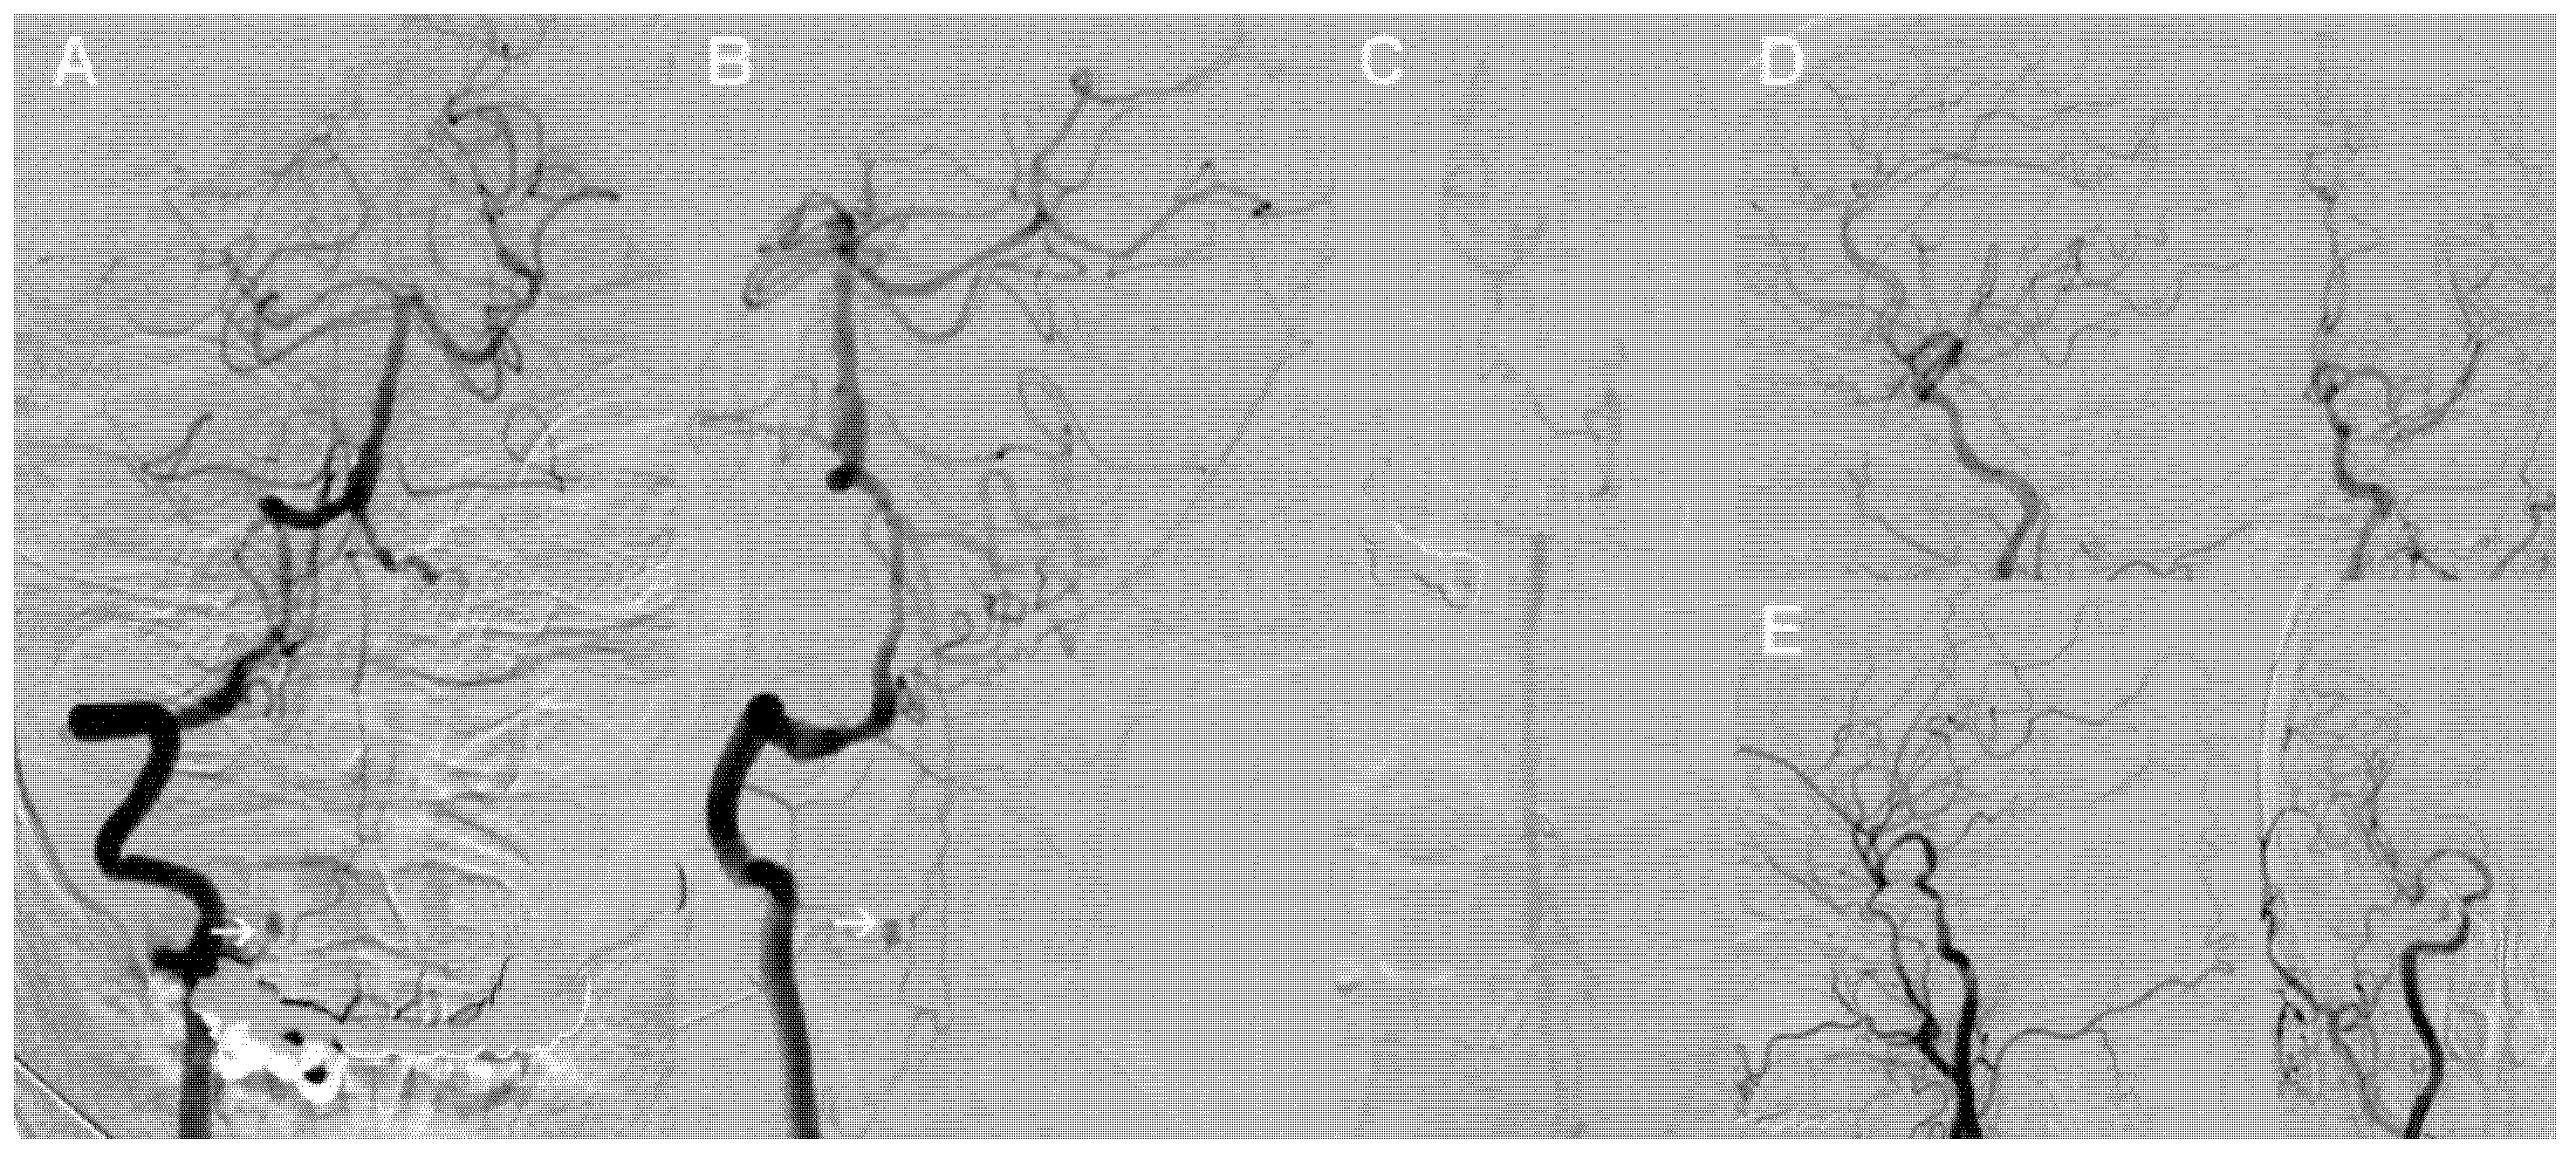

Subsequently, digital subtraction angiography (DSA) was conducted to further clarify the source of bleeding. Right VA angiography demonstrated an isolated saccular aneurysm in the medial V2 segment branch at C2 level with a diameter of approximately 3 mm. The radiculomedullary artery originated from the extracranial portion of the right VA and fed the anterior spinal artery. It clearly showed an isolated aneurysm at the junction between the radiculomedullary artery and the anterior spinal artery (Figure 2A,B). Consistent with the findings of cranial CTA, no obvious aneurysm or vascular malformations were discovered in the left VA and bilateral internal carotid arteries (Figure 2C–E).

Figure 2.

Digital subtraction angiography of the patient. (A,B) Anteroposterior (A) and oblique (B) views of the right vertebral artery show an isolated aneurysm in the medial V2 segment branch. (C–E) No obvious aneurysm or other vascular malformations in the left vertebral artery (C) and bilateral internal carotid arteries (D,E) observed.